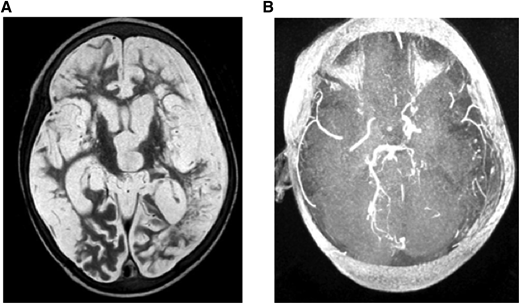

(A) MRI: T2W (axial) and (B) MRA. Brain images from a 7-year-old quadriplegic boy showing (A) global cerebral infarction and (B) occlusion of both terminal internal carotid arteries and small left posterior cerebral artery but no moyamoya collaterals.